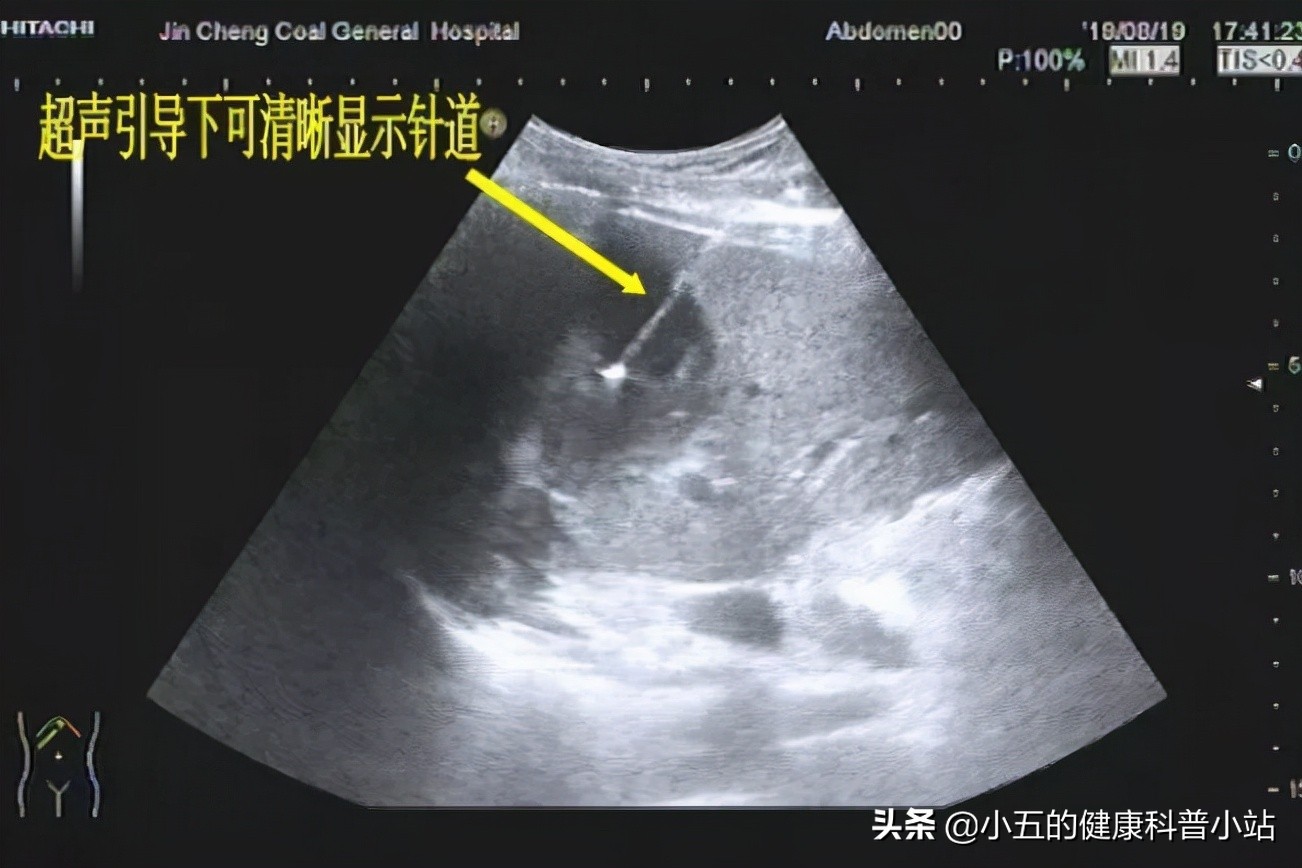

超声引导下穿刺抽吸

临床上建议如果肝囊肿直径大于5 厘米,并出现明显肝脏压迫症状者,可在超声引导下将肝囊肿中的积液抽出,然后向囊内注入无水酒精或高浓度醋酸,以破坏囊肿的囊壁组织,使囊腔闭合 。但对于肿瘤性肝囊肿的患者而言,手术切除是主要的手段,因为肿瘤性肝囊肿的根本原因是肝脏肿瘤导致,因此其往往体积较大,对于肝脏压迫较大,严重时甚至造成肝脏衰竭,因此及时通过手术进行切除是非常有必要的。